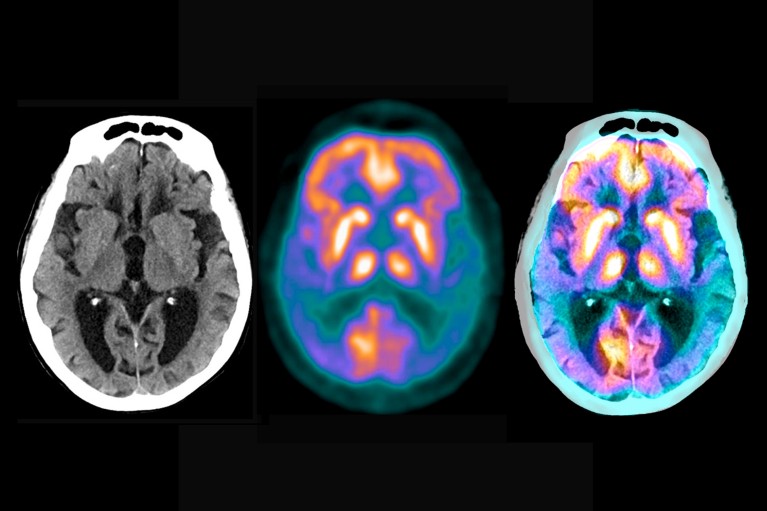

Brain scans reveal the extent of the damage caused by Alzheimer's disease

Key to the trial is a series of sensitive new biomarkers - measurements of the brain or blood that can read the state of the disease. Brain scans monitored the presence and severity of amyloid plaques and tau tangles; Blood or cerebrospinal fluid tests measure many other molecules in the pathological chain, such as different forms of amyloid and tau proteins. The researchers expect that the wealth of molecular and clinical data they generate will help reveal more about the mechanisms of Alzheimer's disease. "Current evidence points to tau as the initiator of Alzheimer's disease symptoms, disability and eventual death," Boxer said. "But this hypothesis needs to be tested in humans."

Typical Signs of Alzheimer's Disease: Plaques (large chunks) and tau tangles (small chunks)